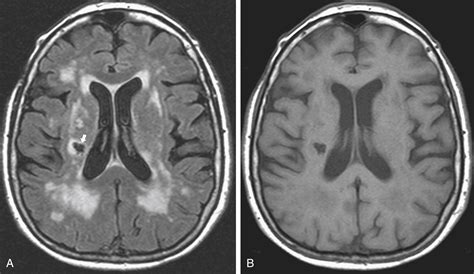

Diagnosing Chronic Microvascular Ischemic Changes

Diagnosing chronic microvascular ischemic changes involves a combination of medical history, physical examination, and diagnostic tests. Some of the common diagnostic methods include:

• Imaging Tests: Such as ultrasound, CT scans, and MRI to visualize the blood vessels and assess blood flow.